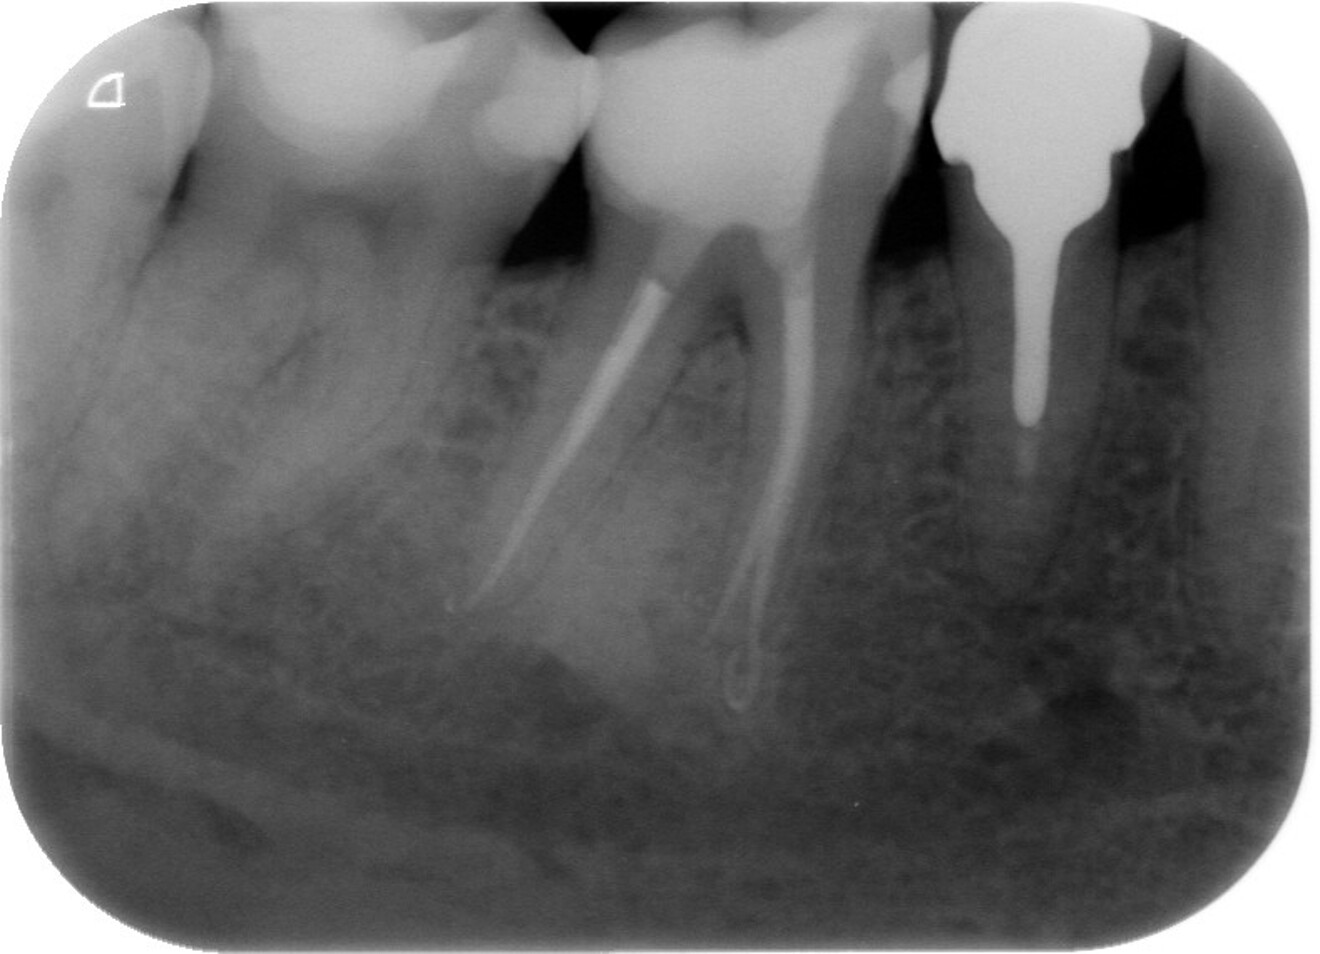

Fig. 1 : Radiographie préopératoire montrant la présence d’une reconstitution corono-radiculaire coulée, ancrée dans les trois canaux.

D’un point de vue pratique, la première étape consiste à réduire les dimensions du tenon s’il occupe une grande partie de la structure coronaire, de préférence en lui donnant une forme cylindrique similaire à celle d’un tenon préfabriqué. De même, une reconstitution corono-radiculaire coulée ancrée dans plusieurs canaux doit d’abord être sectionnée jusqu’au niveau du plancher de la cavité pulpaire, afin de la traiter comme un ensemble de tenons unitaires, ce qui diminue le degré de rétention global du système. La réduction du tenon doit être effectuée avec des fraises en carbure spécialement conçues pour découper le métal, sous une irrigation abondante. Les évaluations cliniques et radiographies préliminaires sont essentielles pour planifier l’angle de coupe. La procédure doit être fréquemment vérifiée et, si nécessaire, il convient d’effectuer des contrôles radiographiques avant qu’une quantité excessive de dentine ne soit sacrifiée (Figs. 1–3).